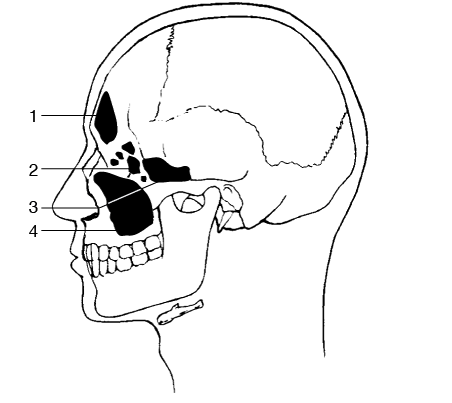

Which of the following would best evaluate the structure labeled 4 in Figure 2–14?

A - PA axial projection (Caldwell method)

B - Parietoacanthial projection (Waters method)

C - Lateral projection

D - Submentovertebral projection

The figure illustrates an anatomic lateral view of the paranasal sinuses. Number 1 points to the frontal sinuses and number 2 to the ethmoidal sinuses; both can be visualized using the PA axial projection (Caldwell method). Number 3 is the sphenoidal sinuses, which are well demonstrated in the SMV projection. Number 4 is the maxillary sinuses, which are best demonstrated using the parietoacanthial projection (Waters method). The lateral projection demonstrates the four pairs of paranasal sinuses superimposed on each other.

The structure labeled 3 in Figure 2–14 is the

A - maxillary sinus

B - sphenoidal sinus

C - ethmoidal sinus

D - frontal sinus

A

Figure 2–14 illustrates an anatomic lateral view of the paranasal sinuses. Number 1 points to the frontal sinuses and number 2 to the ethmoidal sinuses; both can be visualized using the PA axial projection (Caldwell method). Number 3 is the sphenoidal sinuses, which are well demonstrated in the SMV projection. Number 4 is the maxillary sinuses, which are best demonstrated using the parietoacanthial projection (Waters method). The lateral projection demonstrates the four pairs of paranasal sinuses superimposed on each other.